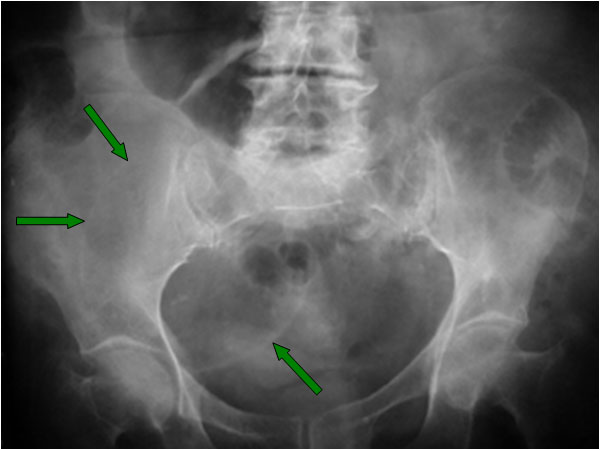

SIGNO DE LA PARED o DEL HALO

Signo de quiste dermoide ovárico en la radiografía simple de abdomen, también conocido como signo del reborde. Consiste en la visibilidad de la pared del quiste, que se presenta como una delgada línea con densidad de partes blandas que rodea al quiste. Esto es posible porque la pared del tumor está delimitada por la grasa del contenido del quiste, por dentro, y la grasa peritoneal, por fuera.

Corte de TC pélvico que muestran el quiste dermoide en la fosa ilíaca izquierda (flechas). Obsérvese como la densidad grasa está presente a ambos lados de la pared.